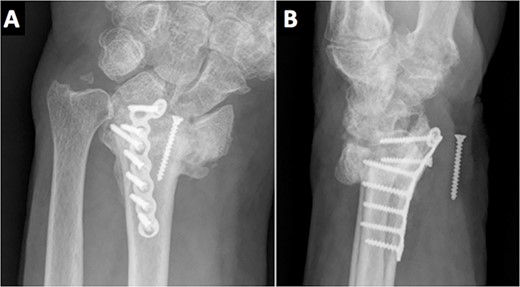

On the third month of follow-up, the loosening of the second most distal screw was observed on plain X-rays. Six months after surgery, radiographic controls showed a migrated screw lodged in the anterior aspect of the wrist. Moreover, the patient complained of anesthesia on the median nerve distribution of the hand (Fig. 3). No motor deficits or atrophy of the thenar eminence were noted. A standard electromyography (EMG) was performed resulting in a complete axonotmesis of the median nerve. During the following 8 months, the patient did not attend the follow-ups. Upon his next follow-up visit, the hypoesthesia on the radial three digits persisted despite the fact that no muscular atrophy or motor deficits were observed, as in his last clinical examination. A new EMG was performed again confirming complete median nerve axonotmesis, and with proximal stimulation, a Martin–Gruber anastomosis in the proximal forearm was discovered [4]. The patient refused further surgery for screw removal.

Radiological evidence of a migrated screw lodged in the anterior aspect of the wrist.